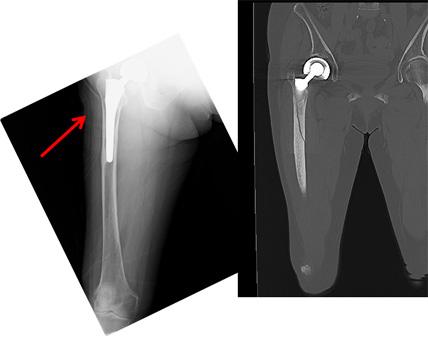

No.12 XPで見えず、CT良く写っている

自宅の洋室と和室の段差で転倒、右大腿部痛、立位・歩行不可、救急要請。

右大腿骨骨幹部に亀裂。

ちょうど人工骨頭のステムに一致。CTで良く写っている。

そこに、過去の骨折治療のための人工骨頭ステムが存在すると骨の観察不適となる。

そのような場合にCTは有効である